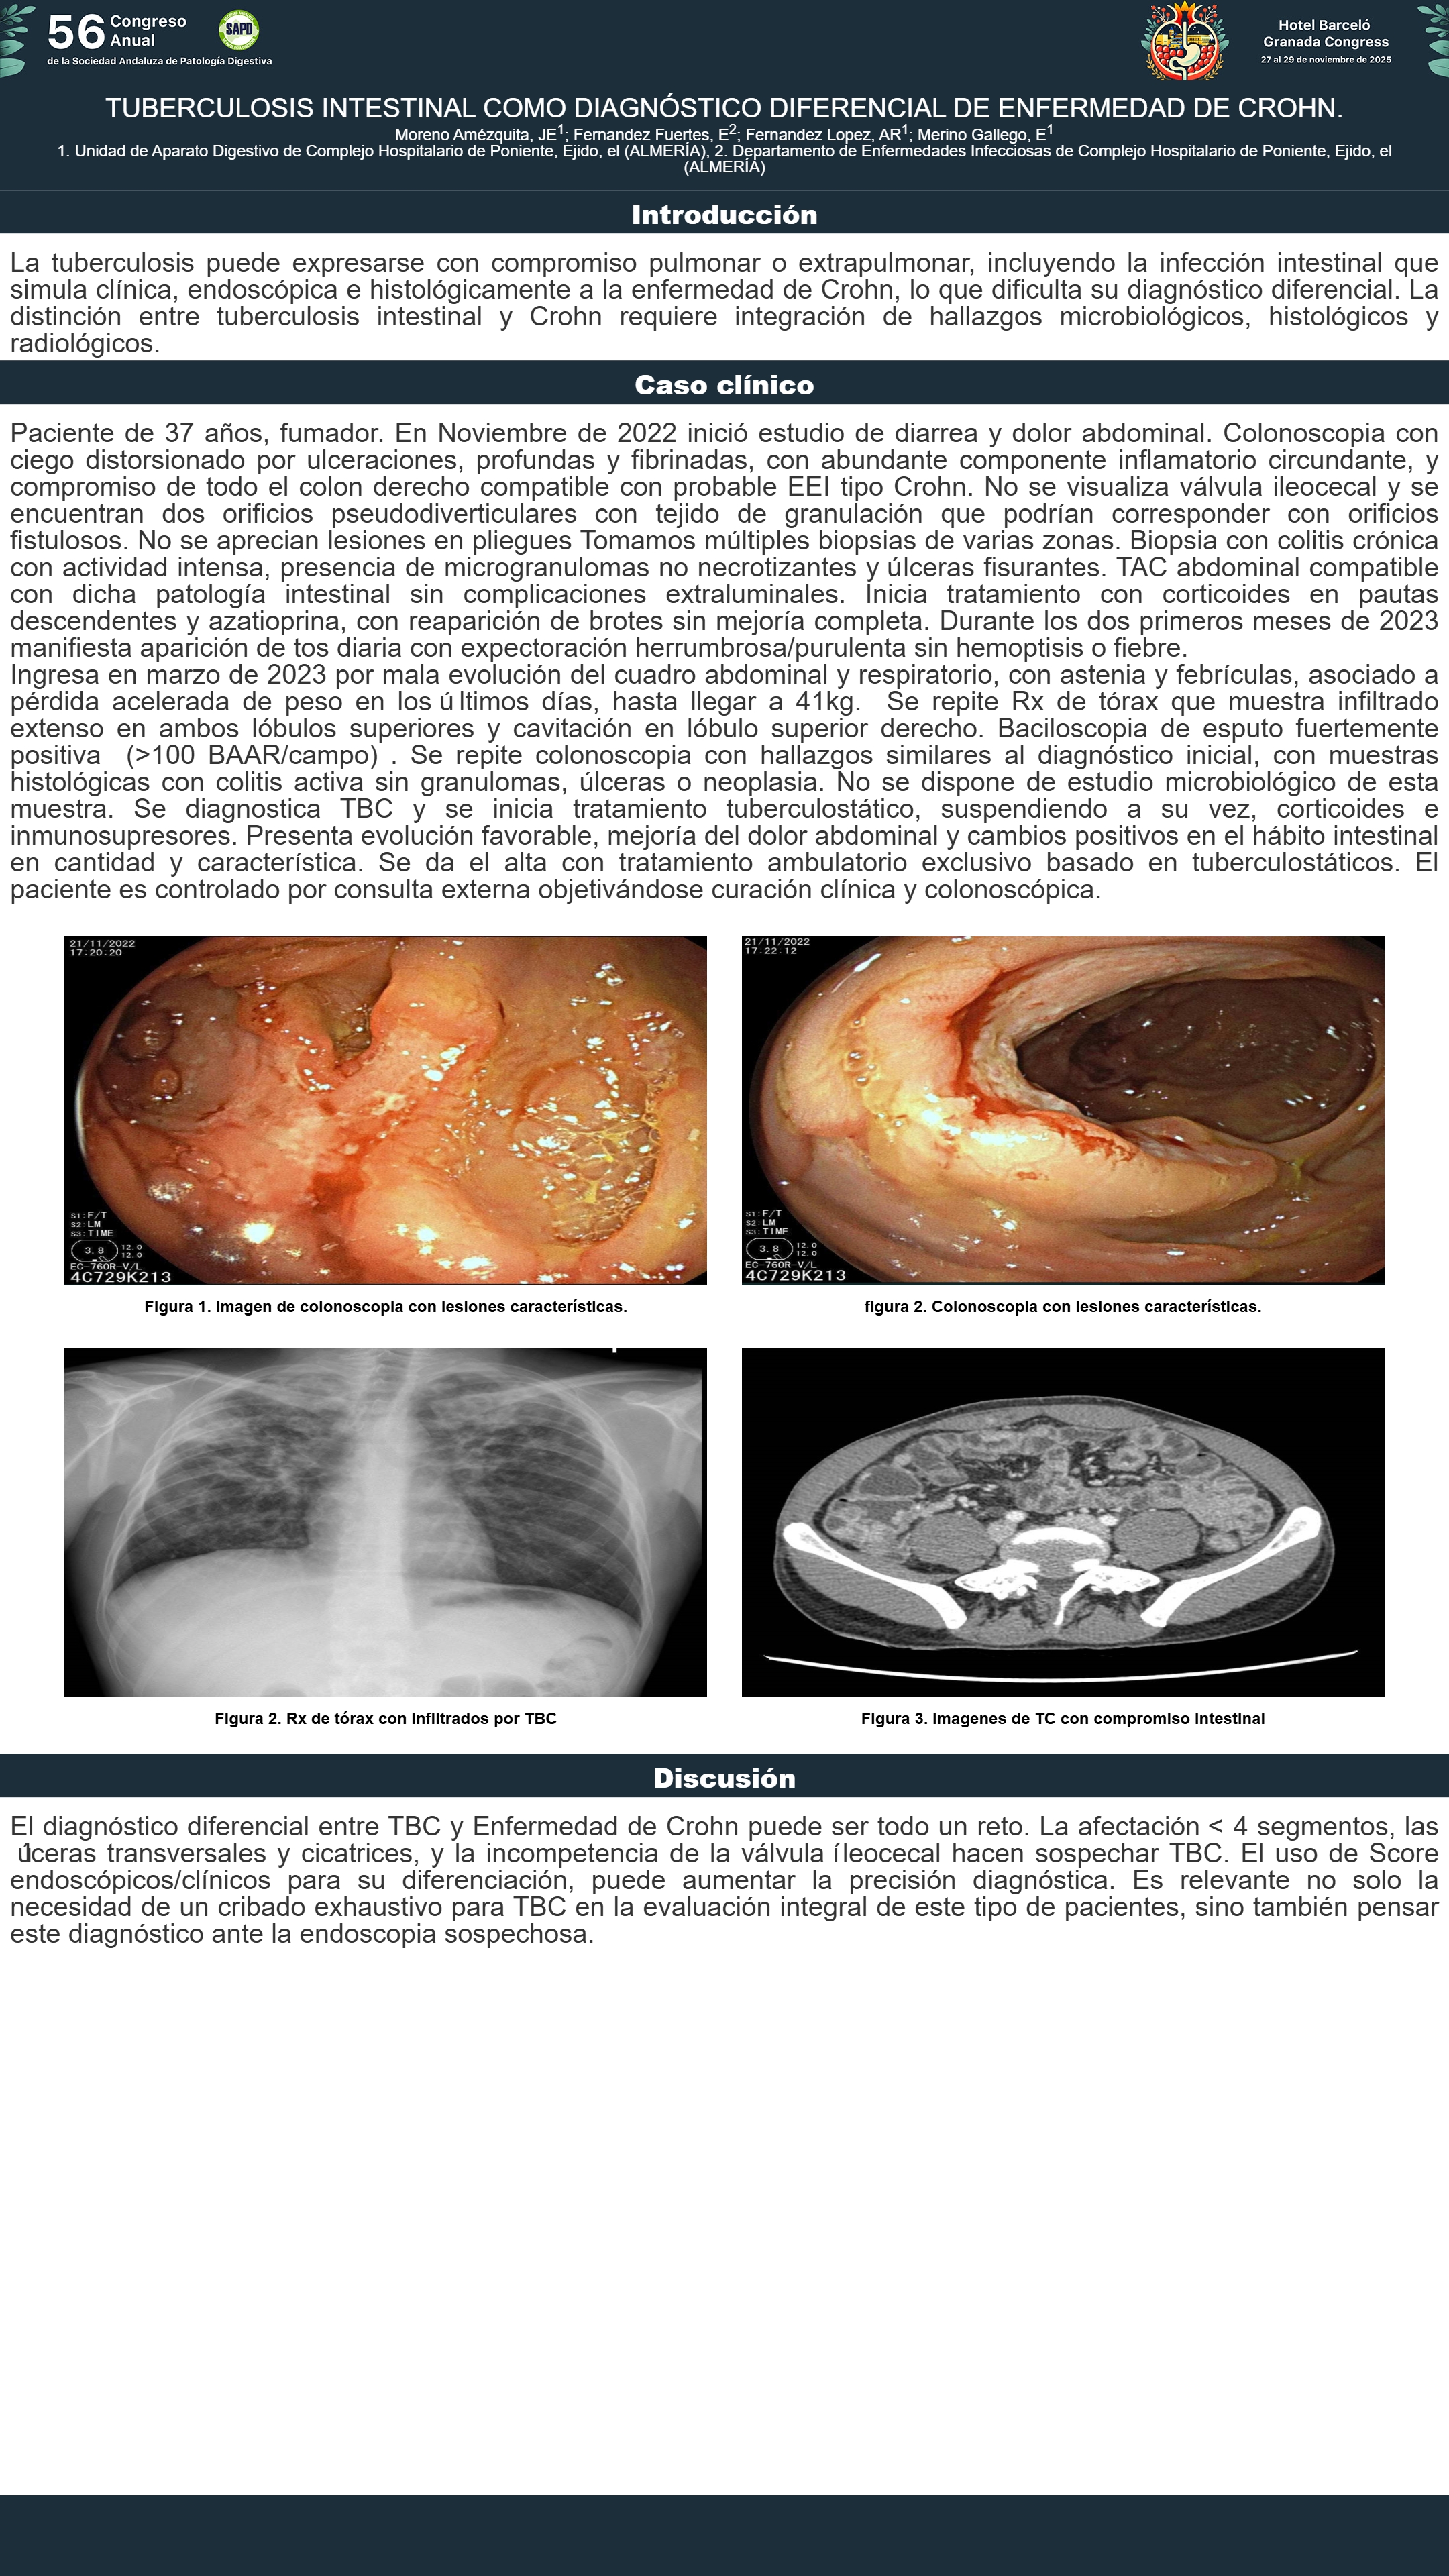

[CP-219] TUBERCULOSIS INTESTINAL COMO DIAGNÓSTICO DIFERENCIAL DE ENFERMEDAD DE CROHN.